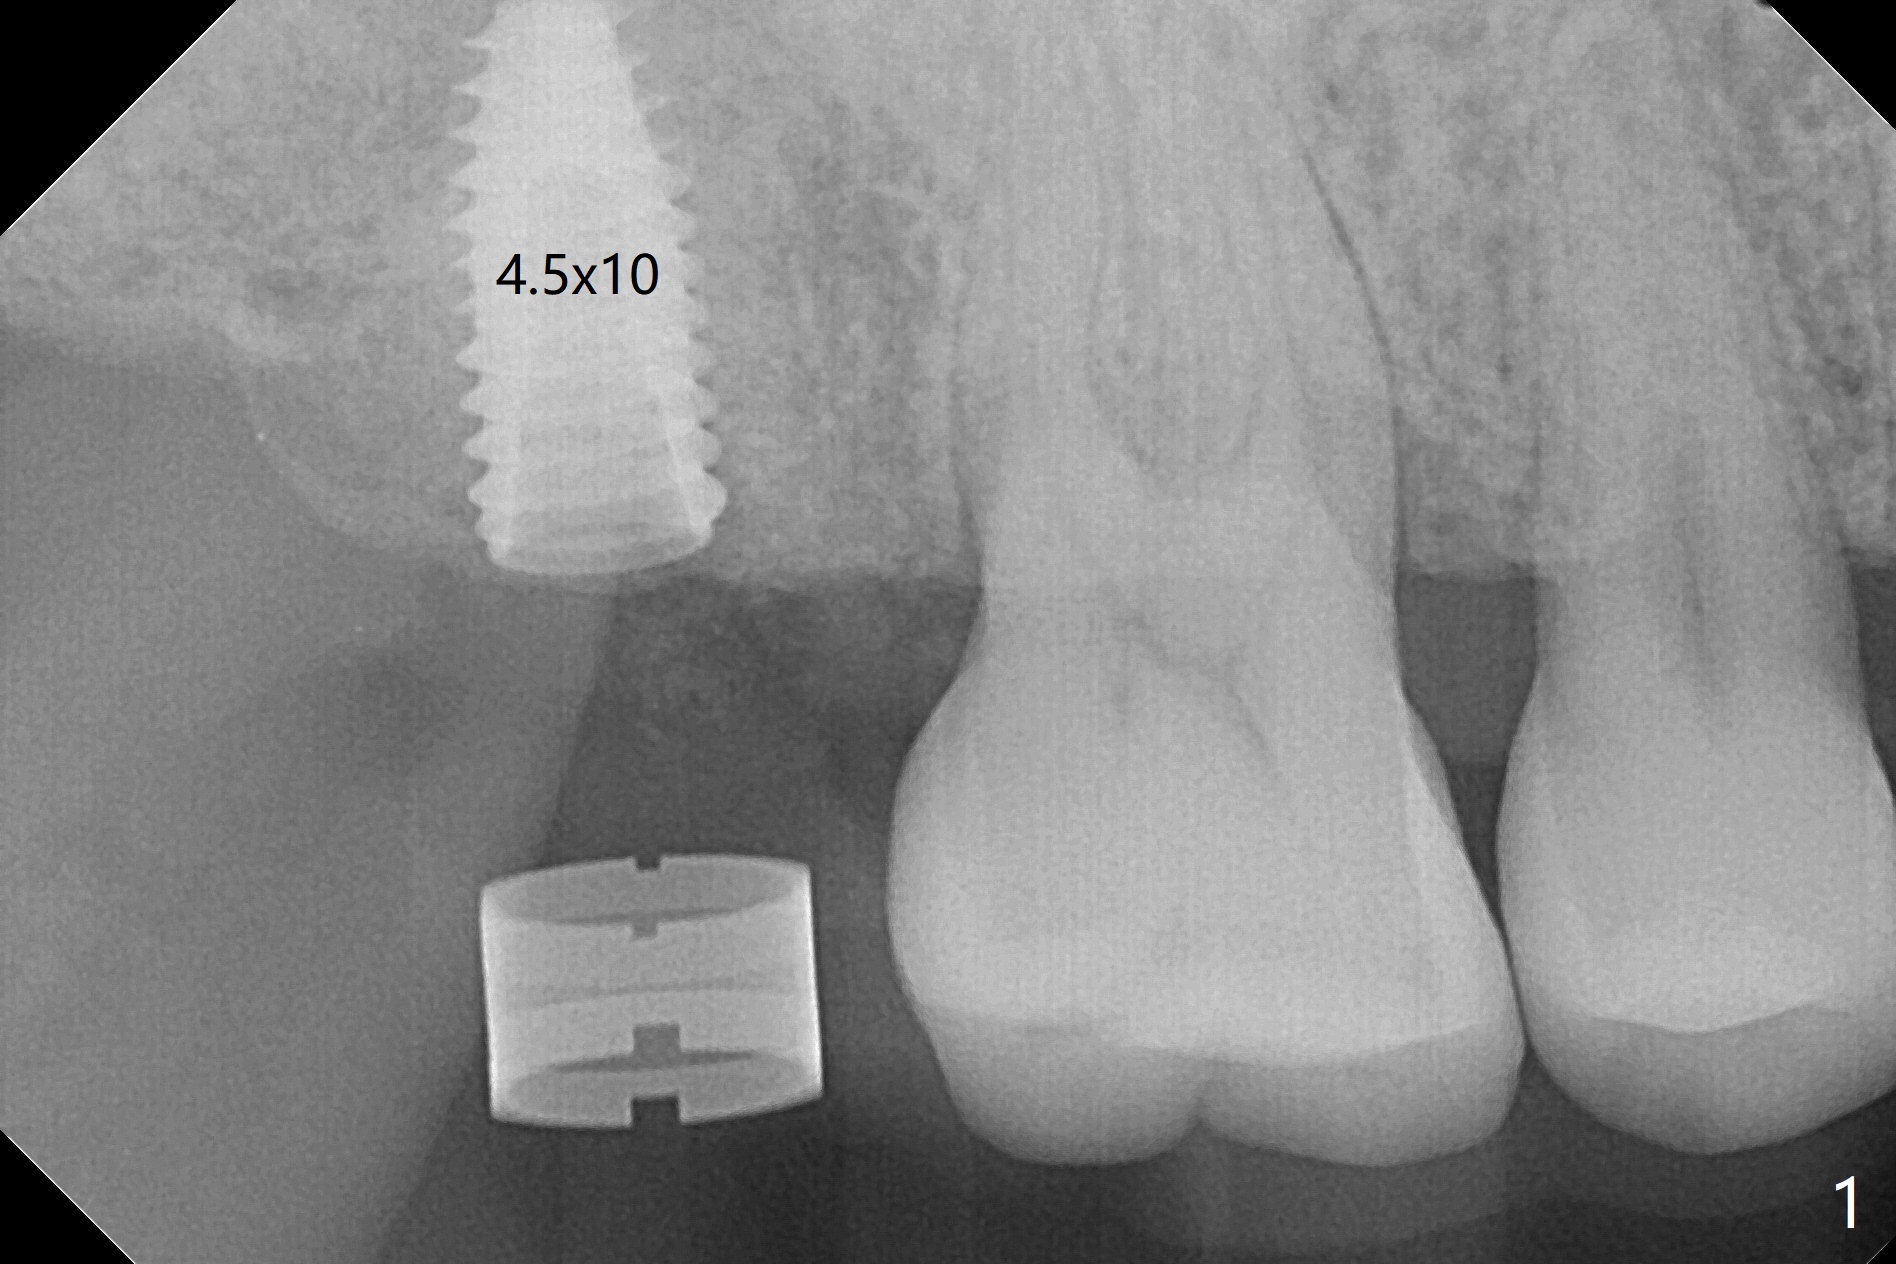

术前CT显示右上7牙槽骨不平,可能造成植体偏移,腭侧,远中螺纹暴露,为了方便导板种植后植骨,切开翻瓣,牙槽骨外形与CT检查一致,不过1.5毫米offset牙槽嵴磨平钻头所形成钻洞正常,除了骨质密度高之外,术中临床和射线检查发现植体方向和种植水平与设计一致,没有偏移(图一至三),最后只有腭侧一个螺纹暴露,放置愈合基台后,放入粘性骨粉,覆盖PRF膜,近中,远中各缝合一针,其余使用牙周胶水关闭伤口。不偏位可能原因:使用1.5毫米offset,骨质密度高,两侧密度接近。术后一周远中伤口裂开(图四:*),近中,远中应该多缝合一针。术后三周伤口愈合。The implant threads are subcrestal 5 months postop (Fig.5).